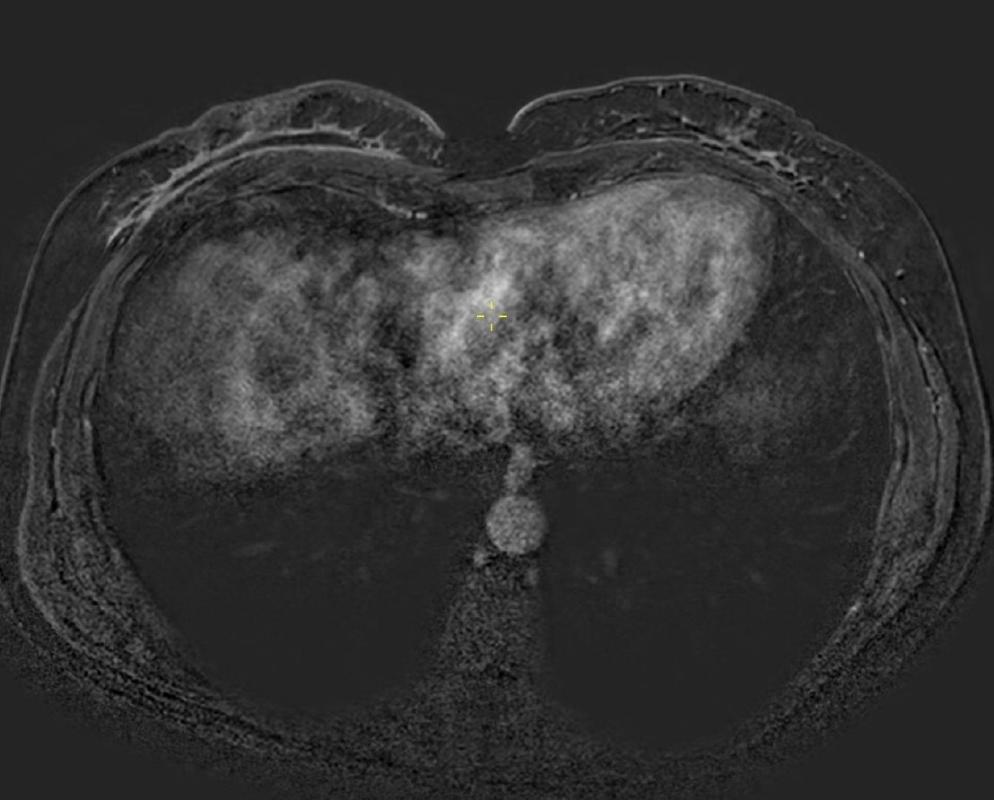

腋下MR影像显示双侧呈球形肿块,在T1WI上表现为低信号。在T1WI对比增强脂肪饱和影像中,可见腋下肿块呈异质性明显强化,伴有点状脂肪区域(图6、7)。